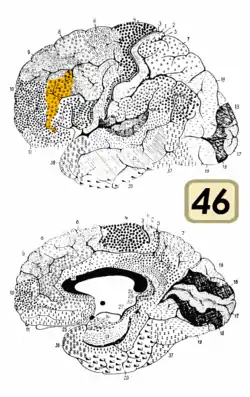

Brodmann area 46, or BA46, is part of the frontal cortex in the human brain. It is between BA10 and BA45.

BA46 is known as middle frontal area 46. In the human brain it occupies approximately the middle third of the middle frontal gyrus and the most rostral portion of the inferior frontal gyrus. Brodmann area 46 roughly corresponds with the dorsolateral prefrontal cortex (DLPFC), although the borders of area 46 are based on cytoarchitecture rather than function. The DLPFC also encompasses part of granular frontal area 9, directly adjacent on the dorsal surface of the cortex.

Cytoarchitecturally, BA46 is bounded dorsally by the granular frontal area 9, rostroventrally by the frontopolar area 10 and caudally by the triangular area 45 (Brodmann-1909). There is some discrepancy between the extent of BA8 (Brodmann-1905) and the same area as described by Walker (1940).[1]